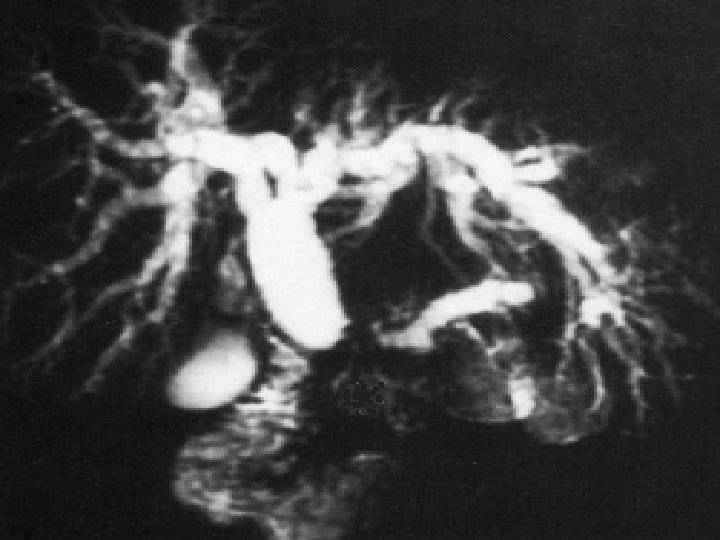

Bili IRM: Ampullome Vatérien